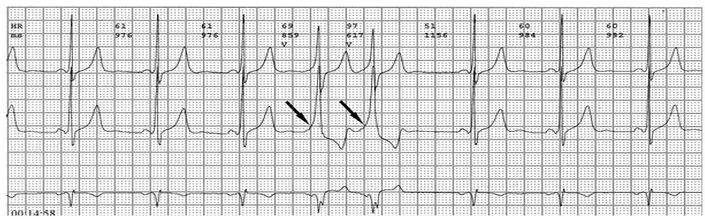

PR间期正常,QRS波群增宽,有预激波。预激综合征室上性心动过速发作时,预激表现大多消失,心电图表现为QRS波群形态正常的室上性心动过速。并发房扑或房颤时,QRS保持预激特征的不少见,心电图表现为QRS波群畸形宽大的房扑或房颤;心室率大多超过200次/分,甚至可达300次/分。房扑时可呈1:1房室传导,并可能辨认房扑波。房颤时心室律不规则,长间歇之后可见到个别QRS波群形态正常(可能为旁路不应期延长,房室结内隐匿传导作用消失后,冲动全部或大部经房室结传导所致),并可能辨认房颤波。心室率极快时,还可伴有频率依赖性心室内传导改变。